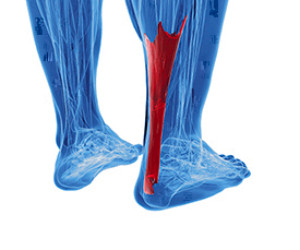

What Happened To My Achilles Tendon?

Patients who have experienced an Achilles tendon injury are familiar with the pain and discomfort that is often associated with it. This tendon connects the heel to the calf muscles, and is considered to be the largest tendon in the body. If it should become inflamed as a result of an injury, Achilles tendonitis may develop. Additionally, it may gradually develop from overuse, and symptoms can consist of pain in the heel area or down the back of the leg. It may feel worse in the morning upon arising, and it will most likely be difficult to flex the foot. Common reasons for this type of injury to occur can include suddenly increasing the intensity of a sporting activity, improper stretching before exercising, or it may come from wearing shoes that do not fit correctly. After a proper diagnosis is performed, the correct treatment can begin which can include a variety of options. If you are afflicted with this condition, it is advised that you consult with a podiatrist who can guide you toward the proper treatment.

Patients who have experienced an Achilles tendon injury are familiar with the pain and discomfort that is often associated with it. This tendon connects the heel to the calf muscles, and is considered to be the largest tendon in the body. If it should become inflamed as a result of an injury, Achilles tendonitis may develop. Additionally, it may gradually develop from overuse, and symptoms can consist of pain in the heel area or down the back of the leg. It may feel worse in the morning upon arising, and it will most likely be difficult to flex the foot. Common reasons for this type of injury to occur can include suddenly increasing the intensity of a sporting activity, improper stretching before exercising, or it may come from wearing shoes that do not fit correctly. After a proper diagnosis is performed, the correct treatment can begin which can include a variety of options. If you are afflicted with this condition, it is advised that you consult with a podiatrist who can guide you toward the proper treatment.

Achilles tendon injuries need immediate attention to avoid future complications. If you have any concerns, contact one of our podiatrists of PA Foot & Ankle Associates. Our doctors can provide the care you need to keep you pain-free and on your feet.

What Is the Achilles Tendon?

The Achilles tendon is a tendon that connects the lower leg muscles and calf to the heel of the foot. It is the strongest tendon in the human body and is essential for making movement possible. Because this tendon is such an integral part of the body, any injuries to it can create immense difficulties and should immediately be presented to a doctor.

There are various types of injuries that can affect the Achilles tendon. The two most common injuries are Achilles tendinitis and ruptures of the tendon.

Achilles Tendinitis Symptoms

- Inflammation

- Dull to severe pain

- Increased blood flow to the tendon

- Thickening of the tendon

Rupture Symptoms

- Extreme pain and swelling in the foot

- Total immobility

Treatment and Prevention

Achilles tendon injuries are diagnosed by a thorough physical evaluation, which can include an MRI. Treatment involves rest, physical therapy, and in some cases, surgery. However, various preventative measures can be taken to avoid these injuries, such as:

- Thorough stretching of the tendon before and after exercise

- Strengthening exercises like calf raises, squats, leg curls, leg extensions, leg raises, lunges, and leg presses

What are Achilles Tendon Injuries

The Achilles tendon is the strongest tendon in the human body. Its purpose is to connect the lower leg muscles and calf to the heel of the foot. This tendon is responsible for facilitating all types of movement, like walking and running. This tendon provides an enormous amount of mobility for the body. Any injuries inflicted to this tissue should be immediately brought up with a physician to prevent further damage.

The most common injuries that can trouble the Achilles tendon are tendon ruptures and Achilles tendinitis. Achilles tendinitis is the milder of the two injuries. It can be recognized by the following symptoms: inflammation, dull-to-severe pain, increased blood flow to the tendon, thickening of the tendon, and slower movement time. Tendinitis can be treated via several methods and is often diagnosed by an MRI.

An Achilles tendon rupture is trickier to heal, and is by far the most painful injury. It is caused by the tendon ripping or completely snapping. The results are immediate and absolutely devastating, and will render the patient immobile. If a rupture or tear occurs, operative and non-operative methods are available. Once the treatment begins, depending on the severity of the injury, recovery time for these types of issues can take up to a year.

Simple preventative measures can be taken as a means to avoid both injuries. Prior to any movement, taking a few minutes to stretch out the tendon is a great way to stimulate the tissue. Calf raises, squats, leg curls, leg extensions, leg raises, lunges, and leg presses are all suggested ways to help strengthen the lower legs and promote Achilles tendon health.

Many problems arise among athletes and people who overexert themselves while exercising. Problems can also happen among those who do not warm up properly before beginning an activity. Proper, comfortable shoes that fit correctly can also decrease tendon injuries. Some professionals also suggest that when exercising, you should make sure that the floor you are on is cushioned or has a mat. This will relieve pressure on the heels. A healthy diet will also increase tendon health.

It is very important to seek out a podiatrist if you believe you have an injury in the Achilles region. Further damage could result in severe complications that would make being mobile difficult, if not impossible.